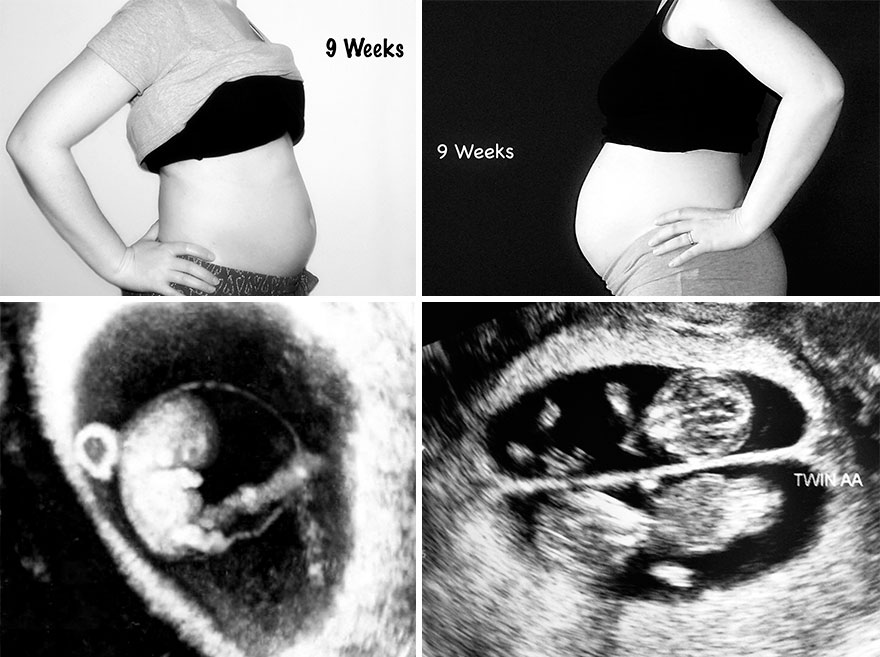

These pictures show the difference in my belly size with my singleton pregnancy and my twin pregnancy. It also shows the week’s corresponding ultrasound pictures. My husband and I continue to be amazed by all we’ve been through to get the amazing kids we have today. Even with the heartache and stress, I would not change a thing. Our three kids, now five years old (singleton) and two and a half (twins) are my world and are truly miracles that would never have been if not for the amazing advances of reproductive medicine. For that, we are truly thankful.

Nine weeks pregnant – Singleton (left) / Twins (right)